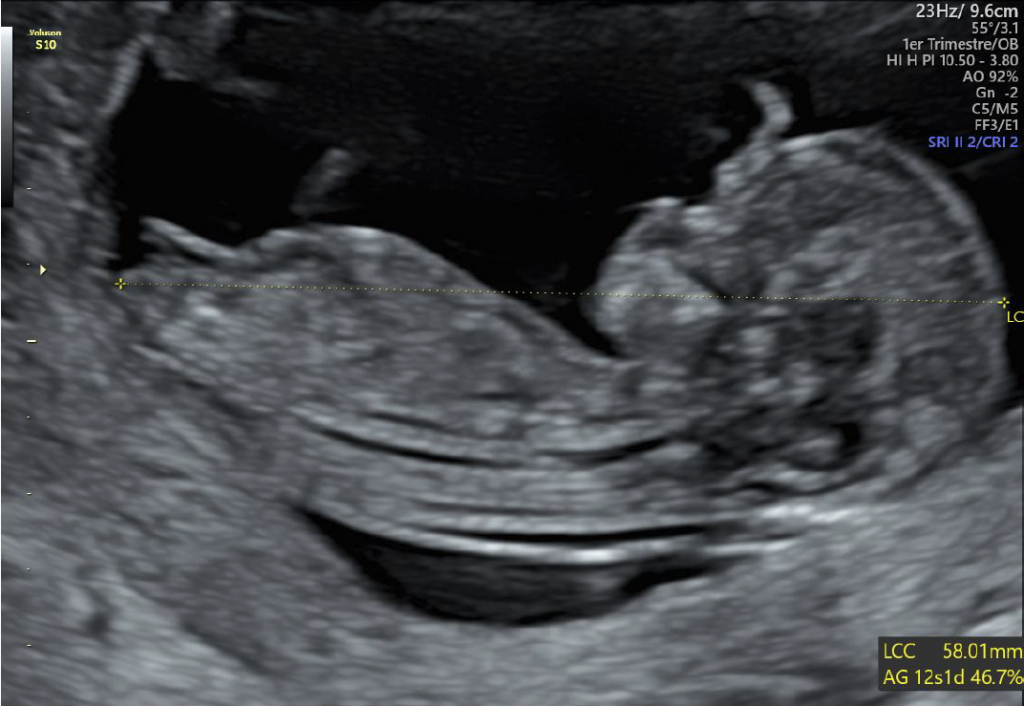

• une échographie de datation afin de confirmer la présence du sac gestationnel dans l’utérus, et de confirmer la probable date de début de grossesse,

• les échographies de grossesse (datation, 1er, 2éme, 3éme trimestre et écho de croissance),